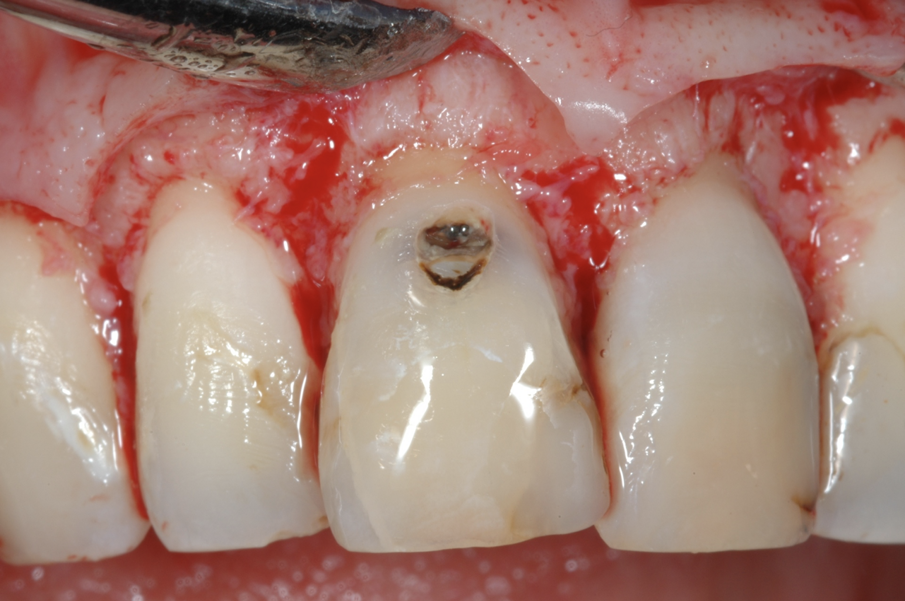

Fig. 4 - Il disegno del lembo chirurgico, sollevato solo sull’aspetto buccale.

Fig. 5 - Il rapporto tra lesione cariosa e tessuto osseo di sostegno appena sollevato il lembo.